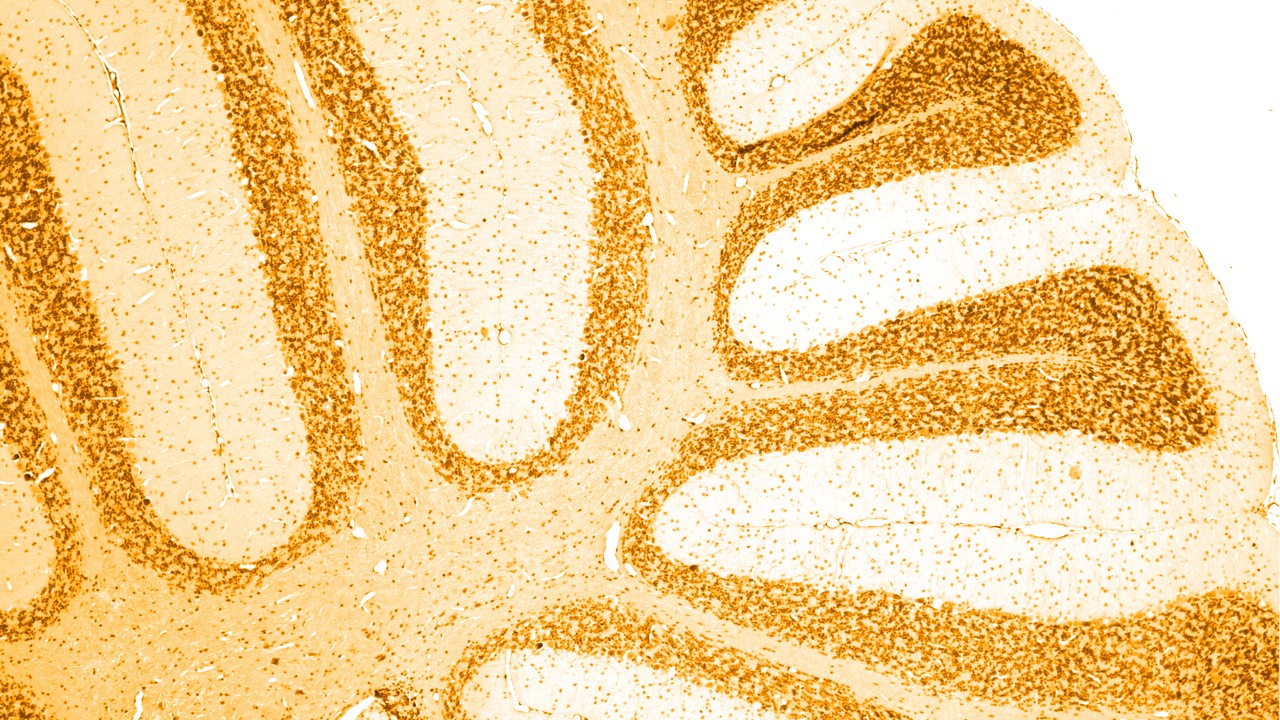

신경계 질환에 대한 이해

신경계 질환은 중추신경계와 말초신경계, 즉 신체 활동을 조절하고 관리하는 뇌와 척수, 신경, 근육에 발생하는 질환입니다.